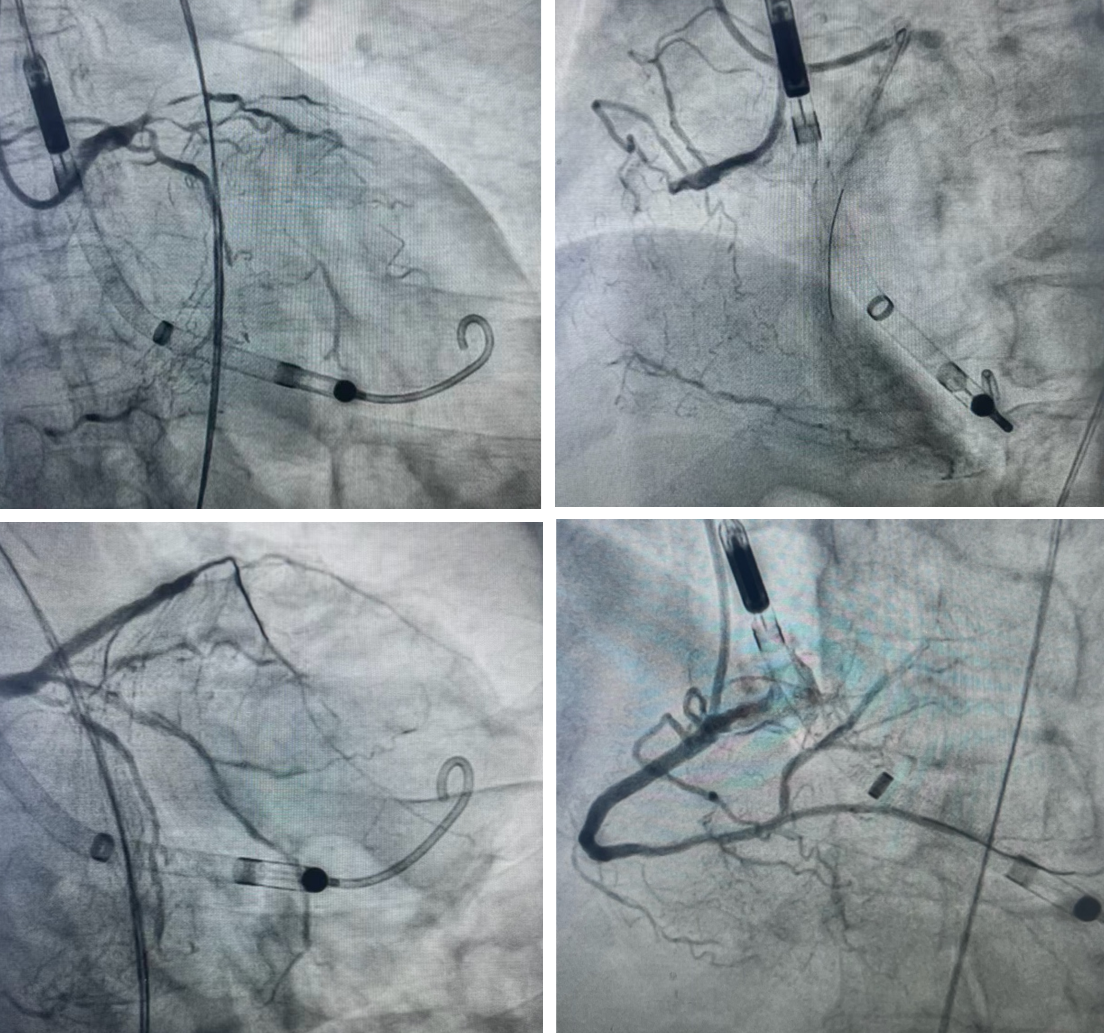

在介入式左心室辅助的坚实支持下,副主任医师朱友琦对最棘手的右冠脉CTO实施介入治疗。CTO病变因闭塞时间久,内部组织常坚硬如橡胶甚至钙化,团队采用了冠脉介入领域的逆向介入技术,在精确的影像引导下操控导丝,通过心脏自身代偿形成的细如发丝的侧支循环血管,从闭塞病变的远端进行“反向”开通。历经数小时精细操作,成功打通血管并植入支架,恢复了前向血流。同时,团队应用血管内超声对血管条件进行精准评估,对前降支和回旋支的严重狭窄处进行了药物球囊扩张与支架植入,最终实现了患者心脏所有主要血管的完全血运重建。

面对极高的手术风险,兰大一院副院长白明、心血管内科监护病房副主任卢安东指导并启用介入式左心室辅助技术作为术中循环生命支持手段。该技术通过导管将微型泵头置于左心室,在心脏搏动的同时,高速旋转的叶轮将血液直接泵入主动脉,部分或全部替代左心室泵血功能,从而维持全身稳定的血液循环和血压,大幅降低心脏自身的负荷和耗氧量,为精细、耗时的操作创造安全稳定的血流动力学环境。